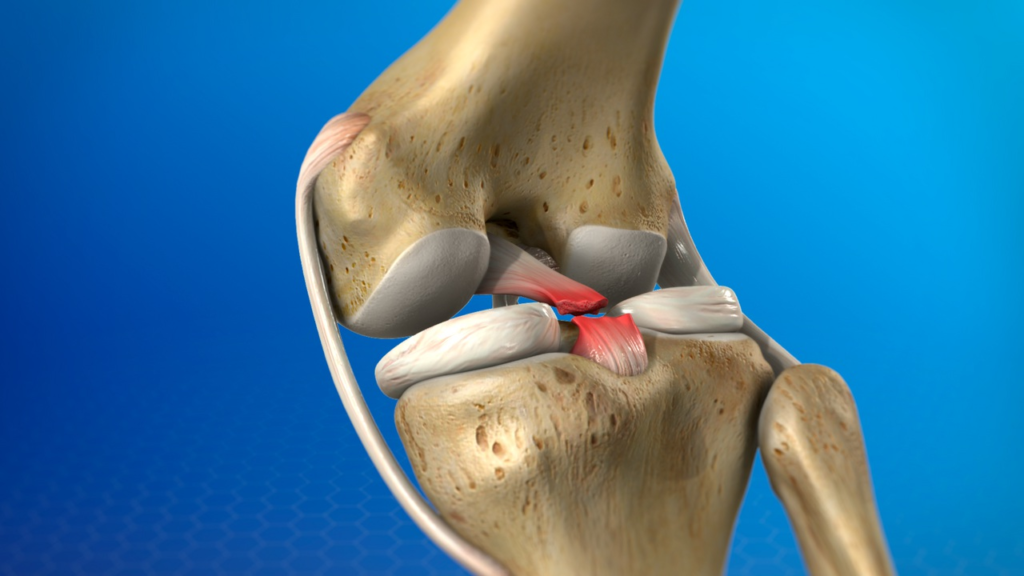

What Is a PCL Injury?

The posterior cruciate ligament (PCL) is one of the main stabilizing ligaments of the knee. It connects the thigh bone (femur) to the shin bone (tibia) and prevents the tibia from moving backward relative to the femur.

A PCL injury occurs when this ligament is overstretched or torn, leading to posterior instability of the knee.

Types of PCL Injuries

PCL injuries are classified based on severity:

- Grade I: Partial tear with minimal instability

- Grade II: Partial tear with noticeable laxity

- Grade III: Complete tear with significant posterior instability

Severity and associated injuries guide treatment decisions.